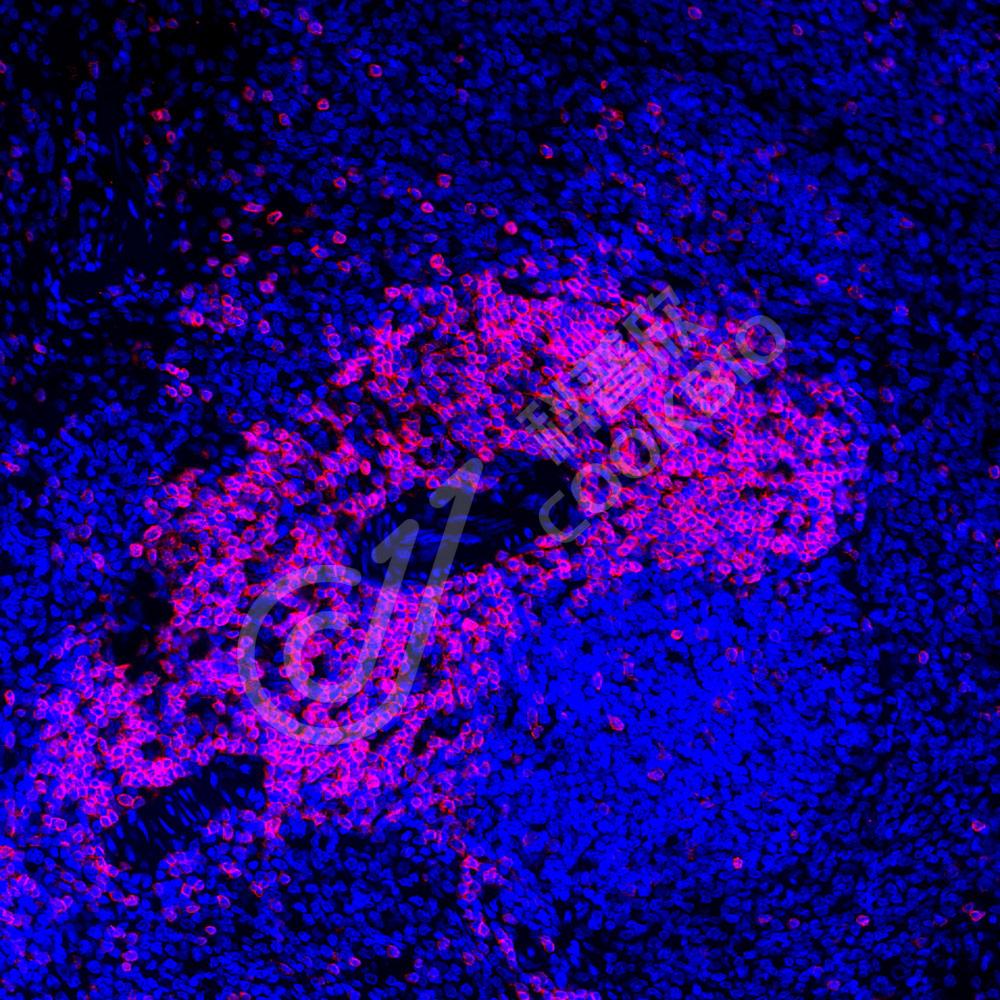

IF检测CD3蛋白(货号 K236042)(红色).

样品: 人结肠癌, 4%多聚甲醛 (货号KSG1101) 固定12-24小时.

抗原修复: 柠檬酸抗原修复液(干粉, pH 6.0) (KSG1201), 高压锅均匀喷气计时2分钟.

封闭: 3% BSA(货号KSGC305010)的PBS溶液, 室温孵育30分钟.

—抗: 1: 1000稀释, 4℃ 孵育过夜.

二抗: Cy3标记山羊抗小鼠IgG (H+L) (货号KB63903), 1: 300稀释, 室温孵育1小时.